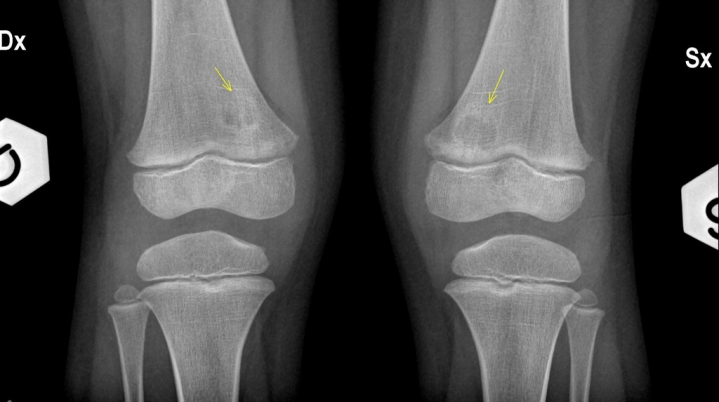

Meniscal ossicle

normal variant - don’t confuse this with a fracture!!

may be associated with meniscal root tears